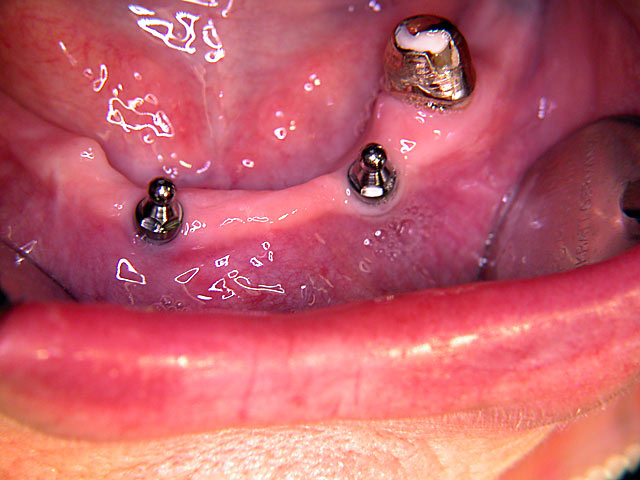

Kugelkopf-Implantation: